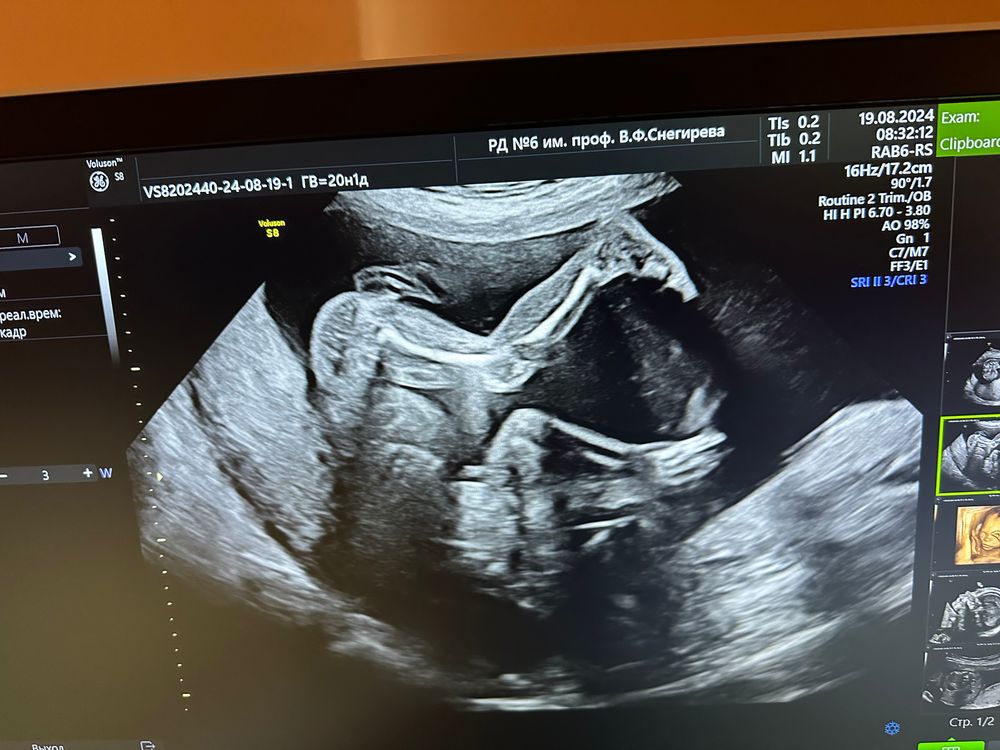

2 скрининг пройден

Какое классное фото с ногами))

Такое фото потрясающее. Твк смотришь и не скажешь, что там всего 330 гр. Прям человечек)

Ничёсе какие ножки мощные. Бегун наверно будущий.

Екатерина Карпова, папа бегал хорошо в детстве, но атлетом не стал :) . Ноги хорошо получились :)